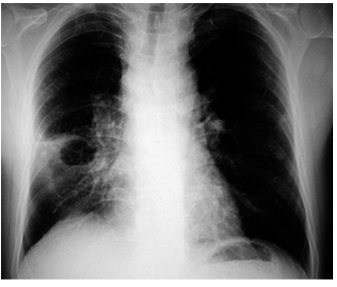

Um homem com 37 anos, em situação de rua de longa data, com condições precárias de higiene pessoal, história de uso abusivo de álcool e de crack, procura atendimento em unidade de pronto atendimento devido a quadro de febre baixa intermitente não aferida, tosse produtiva com escarro esverdeado com rajas de sangue e odor fétido, fraqueza geral e emagrecimento. Ele refere que o quadro tem cerca de 3 semanas de evolução. Realizados os exames, o teste rápido molecular apresenta-se com resultado não detectável para micobactéria e o resultado da radiografia simples do tórax está reproduzida na imagem a seguir.

O paciente é, então, encaminhado para internação hospitalar, sendo iniciado esquema antimicrobiano com Ceftriaxona e Metronidazol por via endovenosa. Após 20 dias de tratamento, o paciente mantém episódios de febre baixa intermitente, mas com menor intensidade, e refere persistirem os sintomas inicialmente descritos, exceto pela redução da hemoptise. Realizada nova radiografia simples de tórax, constata-se que a imagem mostra manutenção das alterações iniciais.